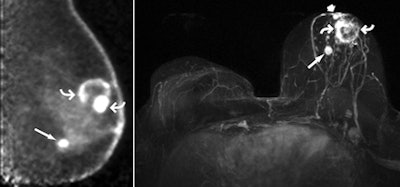

| (above, right) Axial maximum intensity projection of left breast subtraction of precontrast images from 3D spoiled gradient-echo T1-weighted MR images obtained 90 seconds after intravenous injection of 0.1 mmol of gadoversetamide per kg of body weight also shows rim enhancement in known malignancy (curved arrows) and intense enhancement in second, 1-cm mass (long straight arrow) in lower inner region of breast. Metastatic axillary nodes were suspected at MR imaging. The patient opted for direct mastectomy; histopathologic analysis confirmed multicentric grade III IDC, the largest of which was 3.0 cm. The second mass was confirmed to be 1.2-cm grade III IDC with a less than 5% ductal carcinoma in situ component. A third 0.7-cm grade III IDC (straight short arrow) noted in the immediate retroareolar region was difficult to distinguish from normal nipple enhancement but visible on both PEM and MR images. Two of five sentinel nodes showed metastatic disease. Both PEM and MR imaging correctly depicted multicentric disease that was not seen at mammography. All images courtesy of RSNA. |